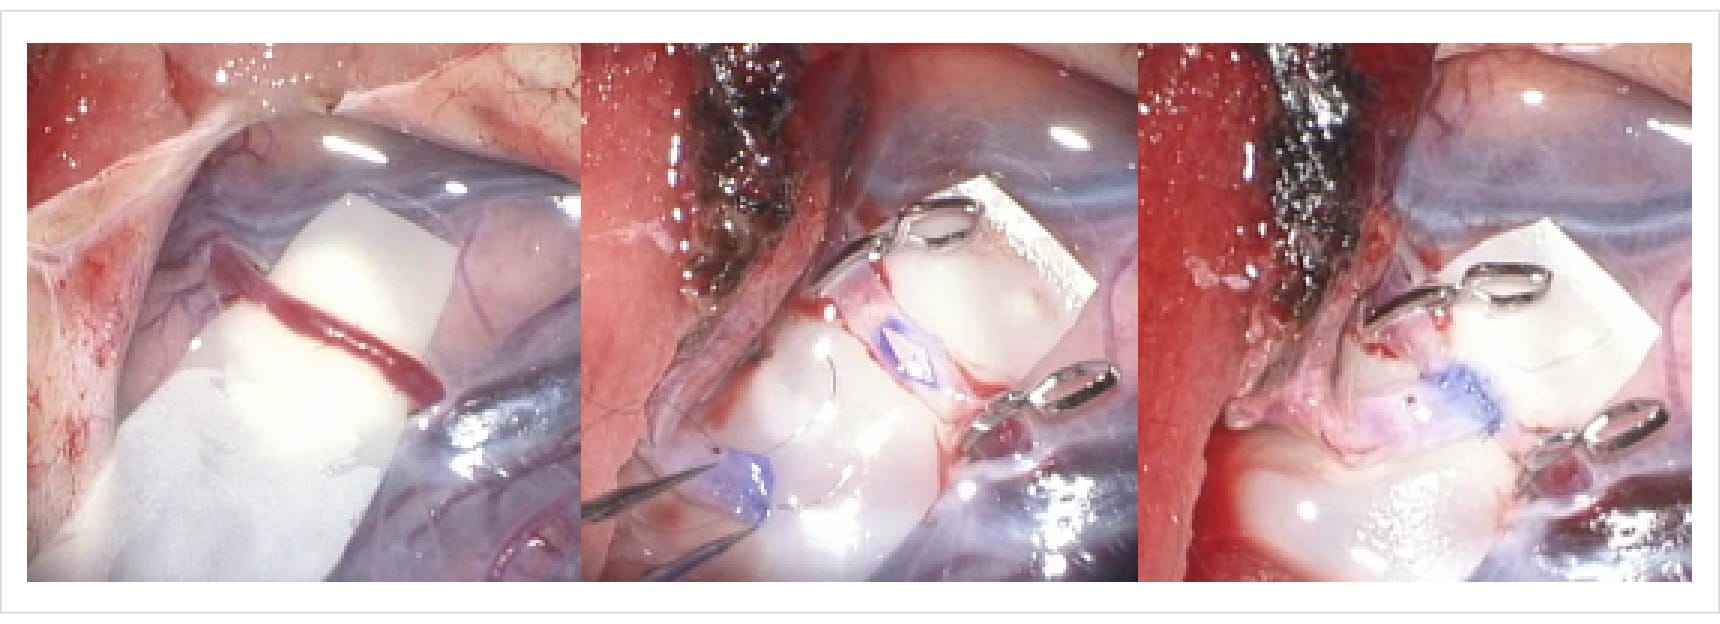

なかでも聴神経腫瘍の治療に関しては、当科が特に高い専門性を有しています。当科主任はこれまでに230例を超える聴神経腫瘍の摘出手術を執刀しており、顔面神経の温存はもちろん、可能な限り聴力の温存も目指した、精緻で丁寧な手術を行っています(図7)。

図7